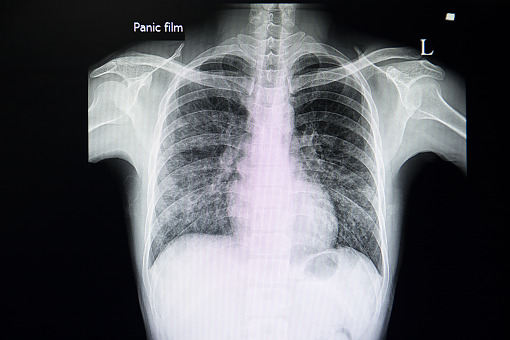

Naukowcy z Uniwersytetu Kalifornijskiego w San Diego stworzyli mikroroboty, które docierają do płuc i dostarczają leki eliminując bakterie wywołujące stany zapalne. Działanie mikrorobotów okazało się bardziej skuteczne niż dożylne podanie antybiotyków – informuje „Nature Materials”.

Zbudowane z komórek alg mikoroboty, na powierzchni których umieszczono nanocząsteczki z antybiotykiem, testowano u myszy z ostrym zapaleniem płuc wywołanym przez bakterie Pseudomonas aeruginosa. Naukowcy dostarczyli mikroroboty do organizmu gryzoni poprzez rurkę umieszczoną w tchawicy.